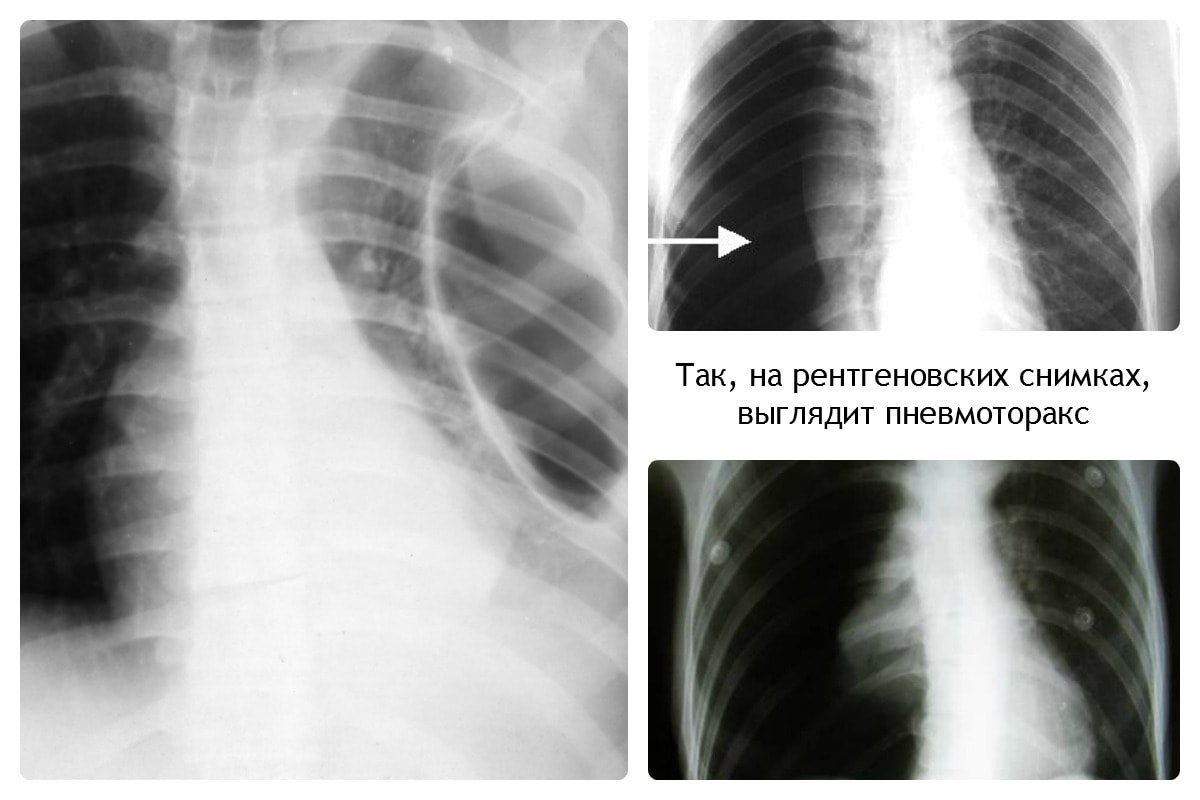

Дифференциация пневмонии от других патологий лёгких

Важным этапом постановки диагноза остаётся отличие её от других заболеваний лёгких, коронавируса. Так, при бронхите будет отсутствовать затемнение на снимке, вместо этого — усиление лёгочного рисунка.

В случае присутствия инородного тела, наблюдается затемнение с чёткими краями, локализующееся в нижней доле лёгкого. Спутать с воспалением типичного характера сложно.

При плеврите, на снимке скопление экссудата в поражённой области. Плеврит выступает в качестве осложнения недолеченной пневмонии.

При пневмотораксе присутствует характерный уровень жидкости. На снимке отображается как просветление, лёгочный рисунок не просматривается.